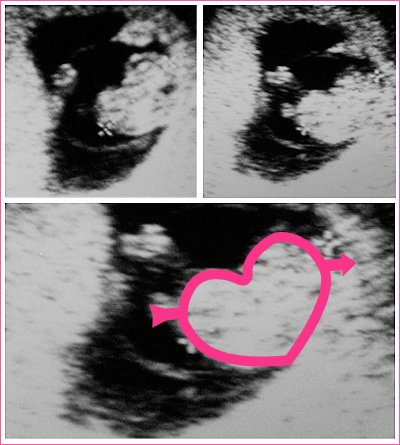

계속 아기집만 보고 아기를 보지 못하고 유산한 터라

아기의 쿵쾅거리는 심장 소리에 정말 목놓아 울었답니다.

모양도 어찌나 이쁜 하트인지요.